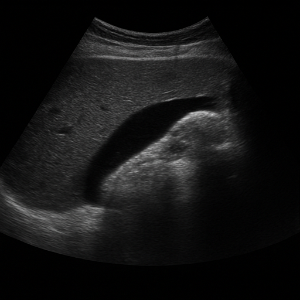

복부초음파는 우리 눈에 보이지 않는 높은 주파수의 소리(초음파)를 배 위에 대고 보내서, 몸속 장기와 혈관 구조를 실시간으로 영상으로 보는 검사입니다. 이 검사는 방사선을 사용하지 않고 통증이나 위험이 거의 없어, 안전하게 여러 번 반복할 수 있어요 .

초음파 기기에는 ‘탐촉자(transducer)’라는 작은 기계가 있는데, 이 기기가 전기 신호로 초음파를 만들어 몸속으로 보내요. 이때 사용하는 주파수는 사람이 들을 수 없는 높은 소리, 보통 2~5MHz 정도예요 .

초음파가 배 안 장기나 조직에 부딪히면 일부는 반사되어 돌아오고, 이 반사파를 탐촉자가 받아 전기 신호로 바꿔요. 컴퓨터가 이 신호를 이용해서 화면에 영상으로 보여줍니다 .

영상이 만들어지는 원리는 시간(반사파가 돌아오는 속도)과 강도(얼마나 세게 반사되었는지)를 컴퓨터가 계산해 이미지의 위치와 밝기를 결정하는 방식이에요. 깊이가 깊을수록 반사되는 시간도 길어지고, 반사파가 세면 화면에서 밝게 나타나요 .